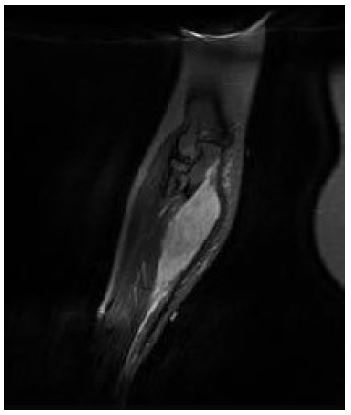

In January 2022, a 19-year-old pregnant female in her 36th week of pregnancy presented with a mass in the right forearm. The mass was investigated using Magnetic Resonance Imaging (MRI), the results of which are shown in Figures 1 and 2, revealing a suspicious lesion in the forearm flexor compartment. A subsequent biopsy was performed, and histopathological analysis confirmed the diagnosis of alveolar rhabdomyosarcoma as can be seen in Figure 3.

Figure 1: Coronal large field of view Proton Density, Fat Suppressed (PD FS) image demonstrating a homogeneously fluid hyper intense lesion at the medial aspect of the right forearm.